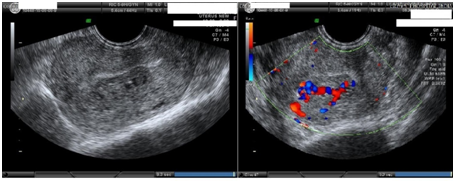

Imaging studies like ultrasound & MRI- pelvis with contrast were done. MRI (Figure 1) was s/o bulky uterus with 4×7×7 cm sized heterogeneous lesion seen in posterior wall, lost endometrial-myometrial interface, multiple dilated tortuous blood vessels in posterior myometrium suggesting possibility of retained products of conception or gestational trophoblastic neoplasia (possibility of Placental Site Trophoblastic Tumor) or uterine vascular malformation. Transabdominal USG of the pelvis (Figure 2) revealed 8.8 cm× 7.5 cm× 7.5 cm bulky uterus the posterior myometrium markedly enlarged and heterogeneous with increased vascularity on Doppler. Doppler showed a peak systolic velocity (PSV) of 121 cm/s and resistive index (RI) of 0.36 i.e. high velocity, low resistance flow. USG also showed that endometrium was thickened (ET-14mm) in the lower uterine segment suggestive of retained products of conception.

Figure 2 USG-pelvis revealed 8.8cm x 7.5cm x 7.5cm bulky uterus the posterior myometrium markedly enlarged and heterogeneous with increased vascularity on Doppler. Doppler showed PSV of 121cm/s & RI of 0.36 i.e. high velocity, low resistance flow. ET-14mm in lower uterine segment.